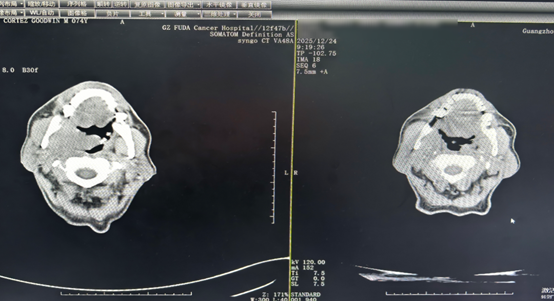

CT comparison after two treatment cycles showing reduction of oropharyngeal tumor and cervical masses

At Fuda, comprehensive examinations revealed that the tumor had invaded the nasopharynx, soft palate, and right-sided muscles, with a high risk of bleeding. Instead of traditional open surgery, the medical team designed a personalized combination treatment plan:

Before long, his right nasal passage became clear, his hearing improved, and the neck masses visibly shrank. Swallowing was no longer difficult, and he could finally eat and sleep comfortably again. Although his voice remained slightly hoarse, his laughter was loud and genuine.